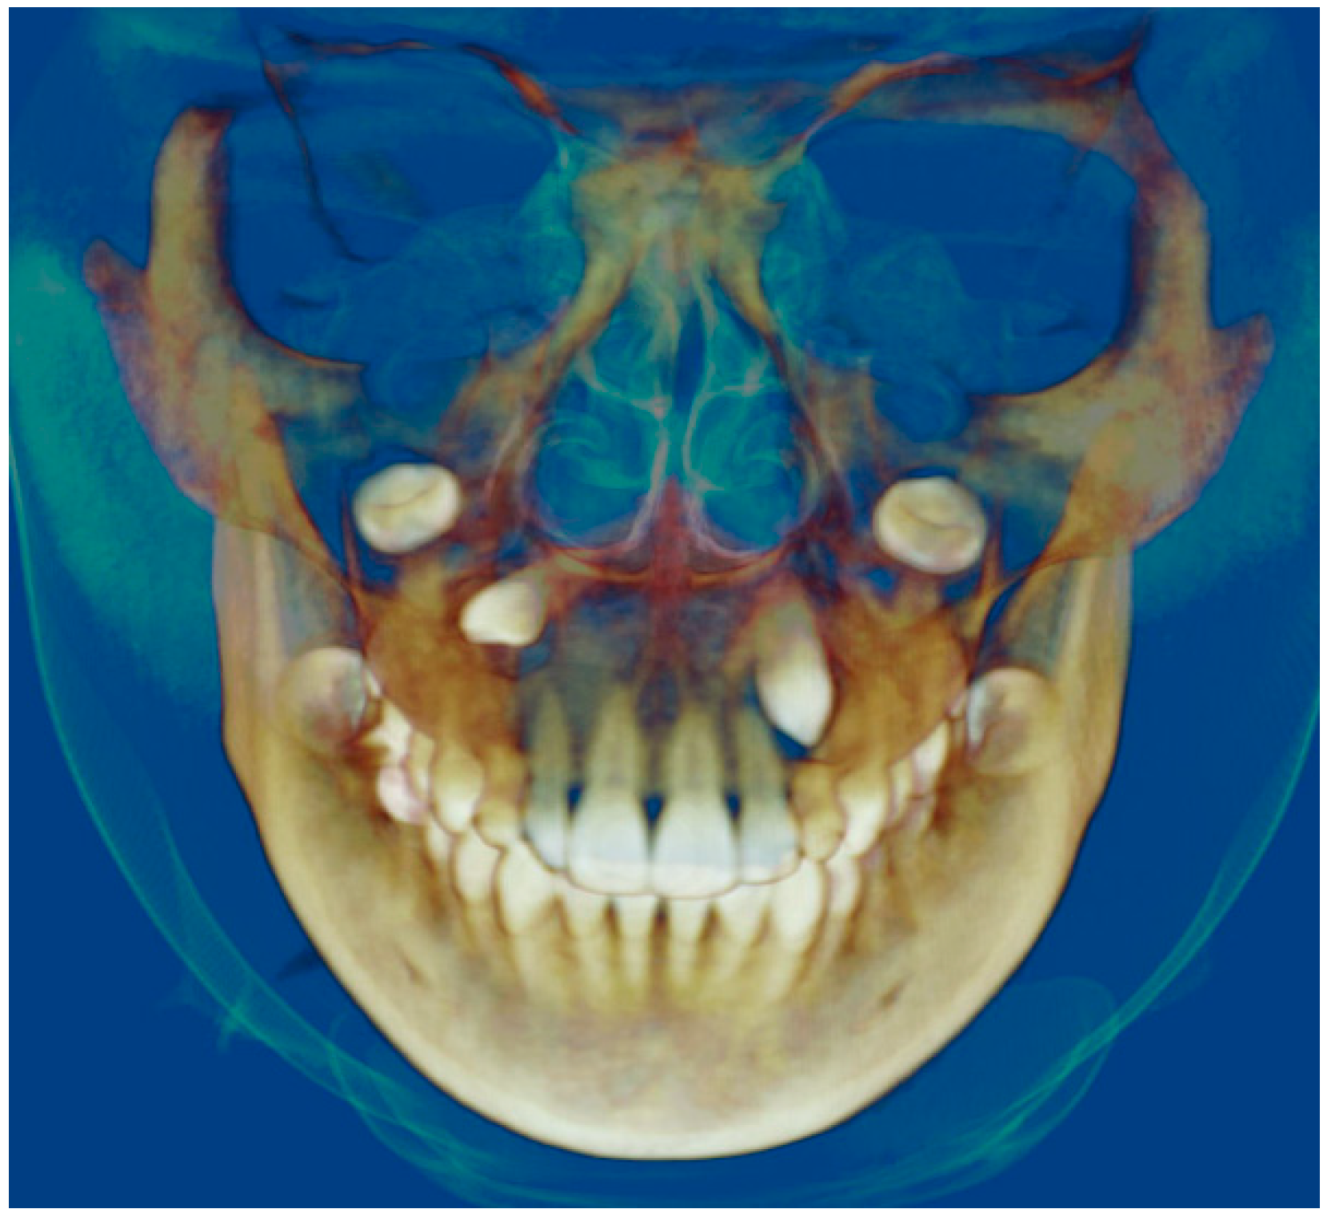

- Evaluation of impacted teeth, a common indication of CBCT in orthodontics. The advantages of CBCT include assessment of the tooth location and position, the stage of development, and status of adjacent teeth. CBCT is justified in these cases, because CBCT has the capability of evaluating the impacted teeth and adjacent structures more accurately than 2D conventional imaging. The benefit–risk ratio is favorable, especially if the CBCT volume is collimated to the impacted tooth. Figure 1, Figure 2, Figure 3 and Figure 4 show an example of impacted maxillary canines, and their proximity to the maxillary lateral incisors. Figure 1 shows an intraoral photograph. The benefit of CBCT acquisition in this case includes the ability to visualize the canines and the lateral incisors in three dimensions, which can be visualized in Figure 2 and Figure 3. In this case, the maxillary right lateral incisor exhibited external root resorption, a finding that would be difficult to see on a conventional 2D panoramic radiograph. Figure 4 shows a Maximum Intensity Projection of a panoramic view derived from the CBCT volume. This unique view is free of magnification, distortion, ghost images, and overlaps frequently seen in conventional 2D panoramic radiography.